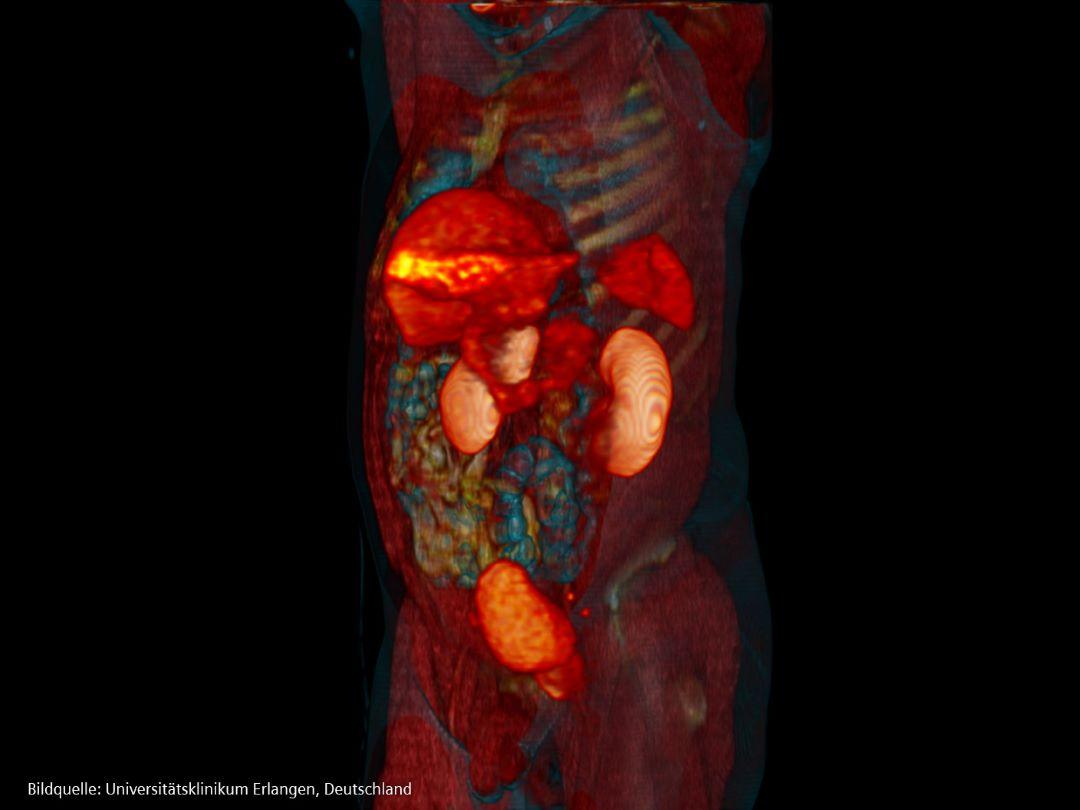

Diagnose und Staging

Am häufigsten wird bei Männern eine lokal begrenzte Erkrankung diagnostiziert, aber bei 10-20 Prozent wird eine metastasierende Erkrankung diagnostiziert. Von denjenigen, die mit einer lokal begrenzten Erkrankung zu kämpfen haben, entwickeln 20-30 Prozent Metastasen [25]. 70 Prozent der Männer, bei denen fortgeschrittener Prostatakrebs diagnostiziert wird, und 90 Prozent der Männer, die der Krankheit erliegen, haben Knochenmetastasen [25].